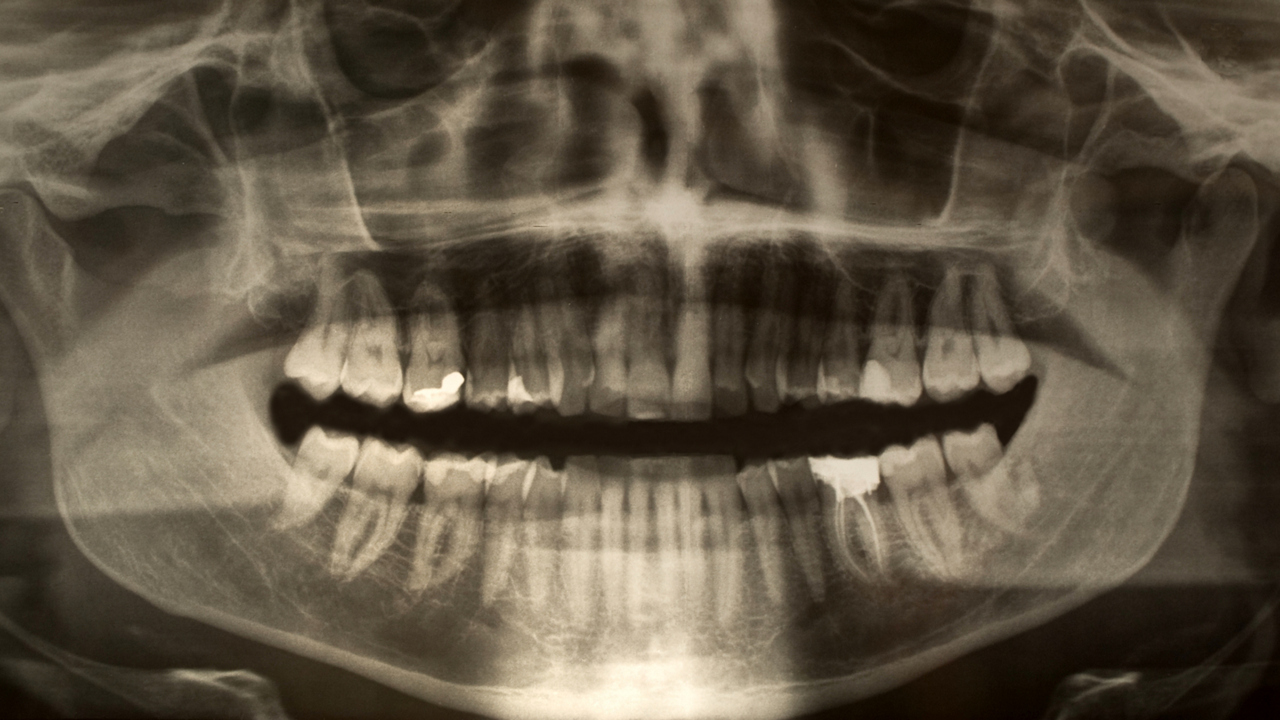

Röntgenbild på käke och tänder.

Tendency for infection and bacterial flora behind caries

Individual variation explains recurrent caries disease and that others are asymptomatic.